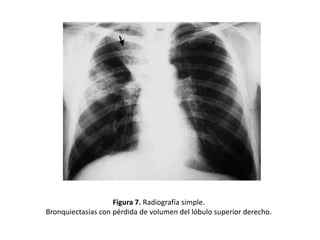

• Signos de pérdida de volumen o atelectasias

(Figura 7)

Figura 7. Radiografía simple.

Bronquiectasias con pérdida de volumen del lóbulo superior derecho.